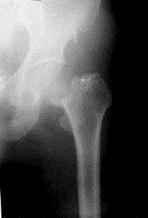

问题 病历摘要: 患者××,女性,70岁,不慎跌倒致伤左髋部后疼痛、活动障碍2天。查体:左下肢呈屈髋屈膝及外旋畸形,右下肢活动时左髋部疼痛,左足跟和大粗隆有叩击痛。 关于股骨头血供正确的是:

选项 A、股骨头血液供应血管在股骨头内不形成吻合,所以股骨颈骨折后易发生股骨头坏死 B、股骨上端之骨髓内动脉 C、动物实验所见:头下骨折后股骨头血液可减少83%,颈中骨折则减少52% D、旋股外动脉发出的下骺动脉供给股骨头之内下1/4~1/2 E、圆韧带动脉(内骺动脉)发自闭孔内动脉,供应股骨头凹窝部分 F、股骨头的血供来自旋股内动脉主干终末支,外骺动脉供给股骨头之外侧2/3~3/4

答案 BCDEF